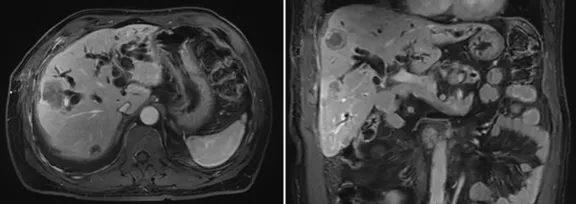

增強CT結果

壺腹部腺癌術后改變,左右肝管匯合部異常信號,不除外復發(fā)可能;考慮肝內多發(fā)轉移瘤形成

所見右側胸腔積液,右下肺片狀異常信號,建議進一步胸部檢查